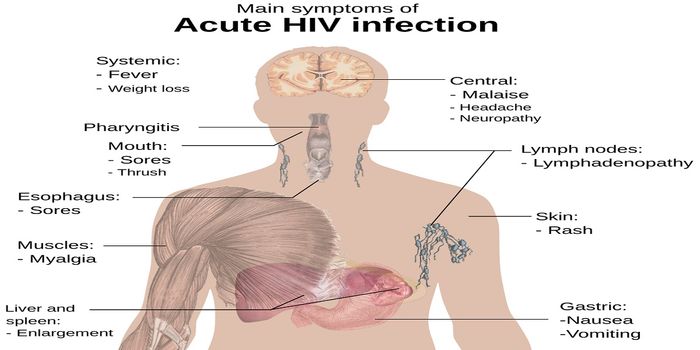

NOV 10, 2019MicrobiologyFor the first time since 2000, researchers have identified a new subtype of HIV.

FEB 02, 2016MicrobiologyUniversity of Minnesota researchers found a new, more affordable way to treat HIV. The RNA-based drug 5-azacytidin ...

DEC 15, 2018Cell & Molecular BiologyResearchers have been trying to create a vaccine for HIV, the virus that causes AIDS, for decades.

MAY 08, 2019Health & MedicineThe ability to diagnose an acute HIV-1 infection before there are detectable antibodies to HIV 1/2 is critical to making ...